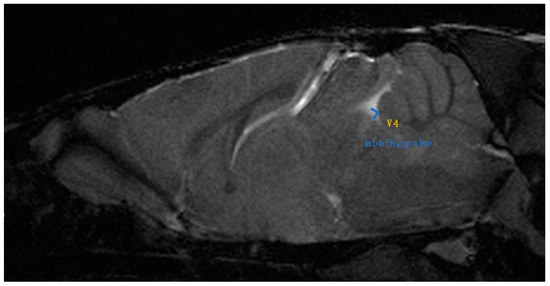

Two board-certified physicians and one senior author who specialized in the imaging of the CNS in laboratory animals independently measured the images of 30 mice (10 wild-type and 20 twy/twy mice) taken with the Time-SLIP technique 3 times. The examiners were blinded to the genotype of the mice. We defined the stir distance as the distance of CSF stirring in the sagittal plane within a single time period (3 s) in the fourth ventricle, where there is relatively more space, and three examiners took measurements 3 times for each mouse (Figure 2). Furthermore, the examiners also measured the antero-posterior diameter of the spinal cord and spinal canal on the MRI sagittal plane and calculated the canal stenosis ratio (CSR). (Figure 3) We examined the correlation between stir distance and CSR using Pearson’s correlation coefficient. Additionally, to eliminate the potential impact of respiration on the dynamics of CSF, the respiratory rates of wild-type and twy/twy mice were recorded and compared.

Figure 2. The distance of CSF stirring in the sagittal plane within a single time period at the bottom of the fourth ventricle. Stir distance (two-headed arrow shows stir distance). (A) Stir distance in 12-week-old wild-type mouse, (B) stir distance in 12-week-old twy/twy mouse.